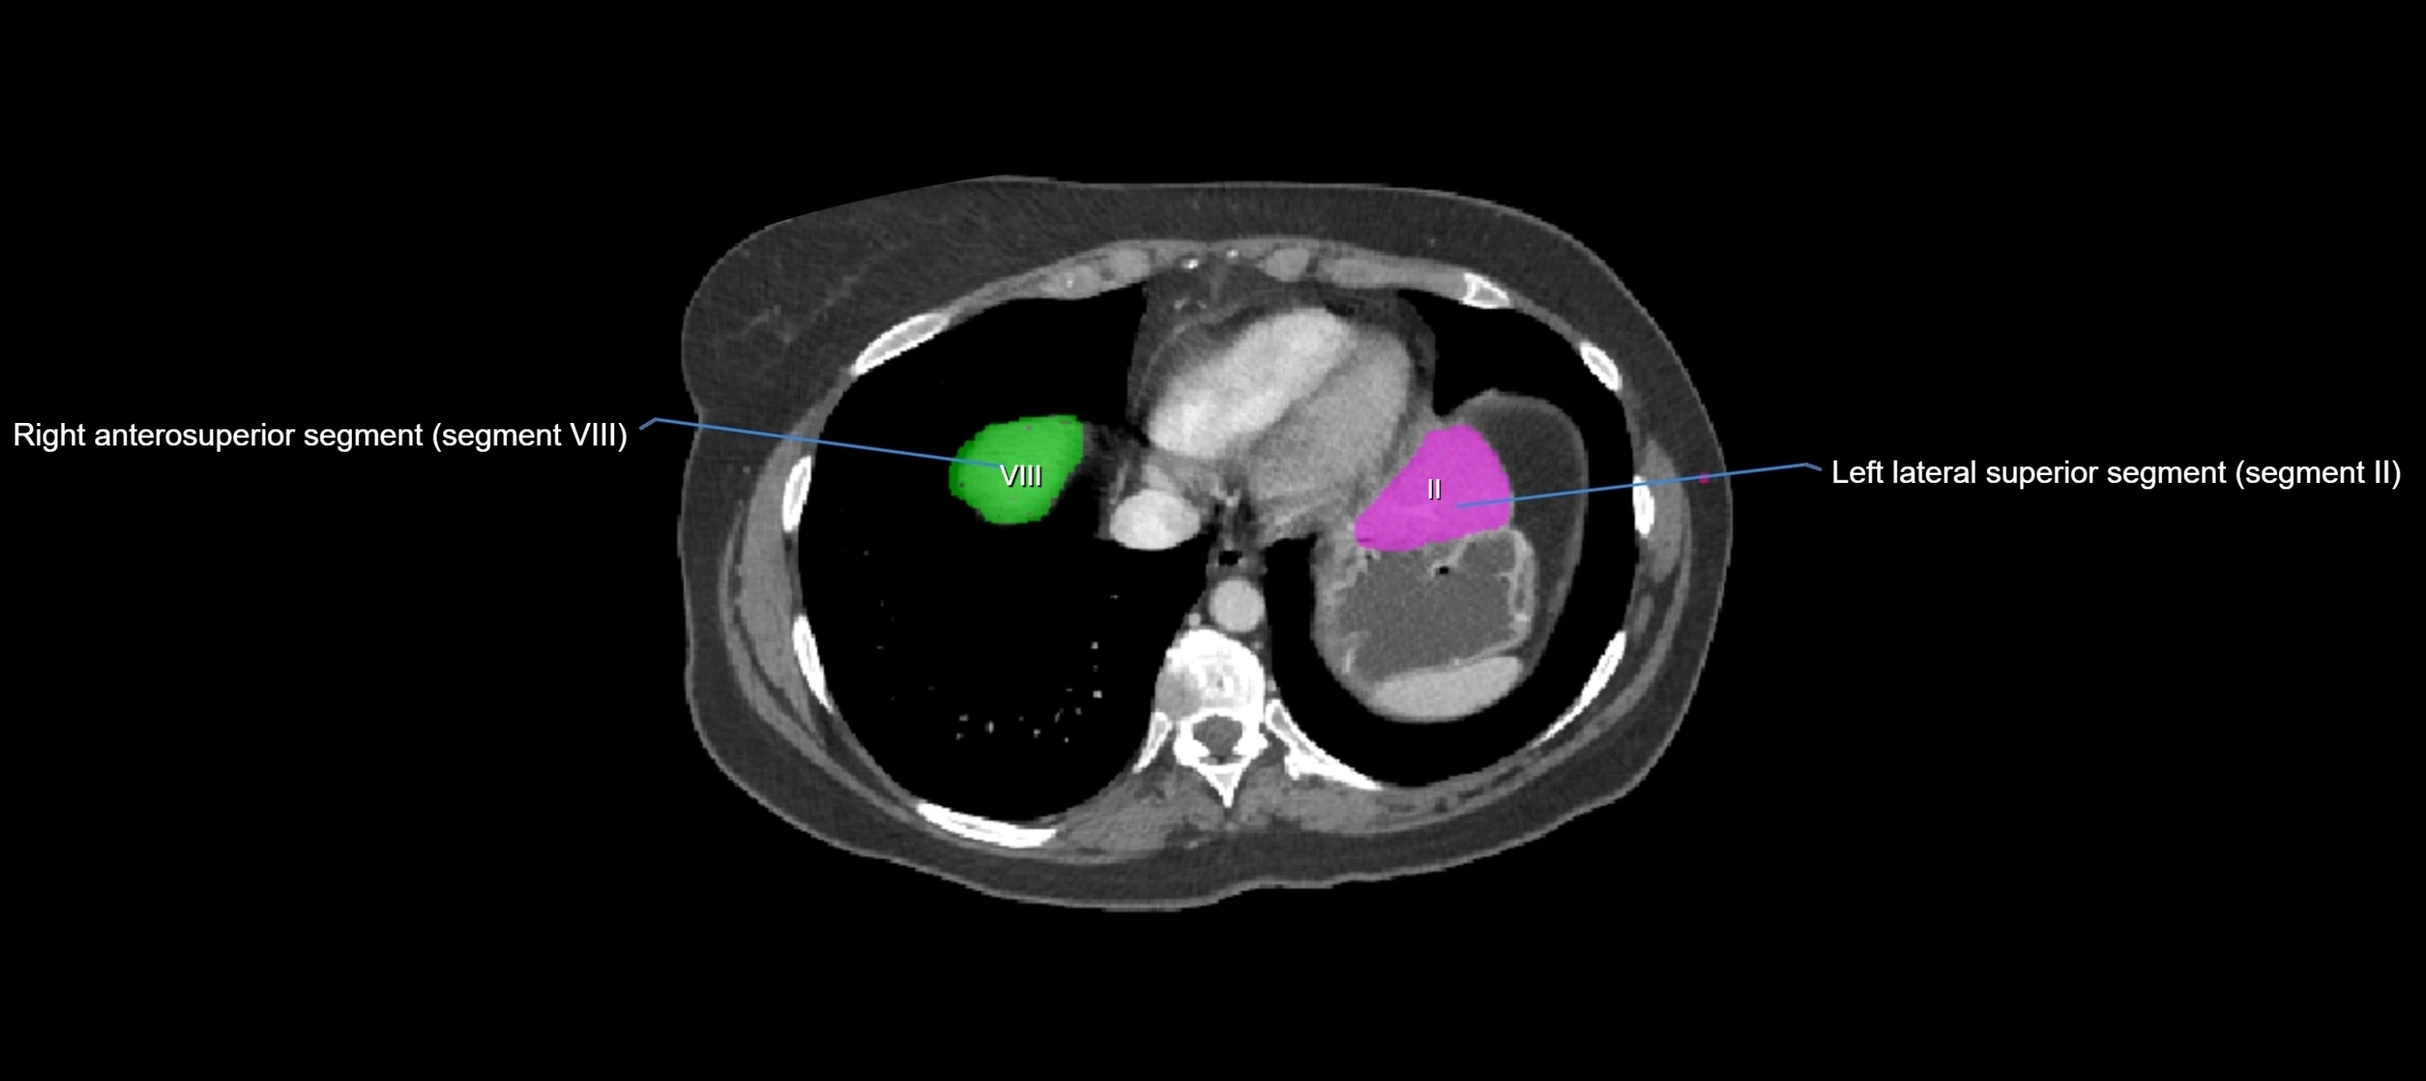

CT Image

image